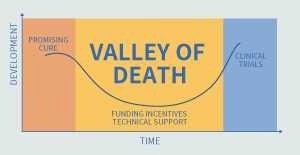

On the other hand, better screening hits are needed to cross the “valley of death” in the drug development process.

To achieve this, more intricate assessment methods must be developed, including live-cell imaging, 3D cultivation systems, and higher-detail image processing to leverage numerous aspects.

Determining the best way to conduct parallel throughput and complicated evaluation system screening in drug development research is a crucial problem.